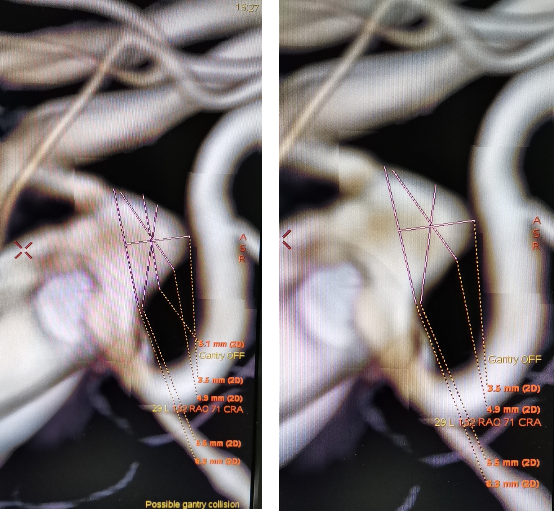

全脑血管造影:右侧大脑中动脉M1分叉处动脉瘤,瘤体3.3 mm*4.1 mm,瘤颈2.7 mm。前交通动脉瘤栓塞完全。

全麻满意后,常规消毒铺巾,采用改良 Seldinger技术穿刺右侧股动脉成功,置入6F动脉鞘。黑泥鳅导丝带领5F单弯导管行脑动脉造影,右侧颈内动脉造影见:右侧大脑中动脉M1分叉处动脉瘤,瘤体3.3 mm*4.1 mm,瘤颈2.7 mm。前交通动脉瘤栓塞完全。

经右侧股动脉鞘,黑泥鳅导丝带领导引导管(Codman 6F Envoy DA)到达右侧颈内动脉岩段,微导丝(Synchro--14 0.014 in*200 cm)带领支架微导管(Excelsior SL--10)到达右侧大脑中动脉M2段,退出微导丝。微导丝带领弹簧圈微导管(Echelon10)到达右侧M1远端分叉处动脉瘤内,退出微导丝。经弹簧圈微导管填入弹簧圈(Codman 3 mm*4 cm)经支架微导管输送支架(Neuroform Atlas 3.0 mm*15 mm)并释放在M2段至M段中部,完全覆盖动脉瘤颈。继续经弹簧圈微导管依次填入弹簧圈数枚,间断造影确保右侧大脑中动脉及远端血流通畅。右侧颈内动脉造影确认:动脉瘤致密填塞,载瘤动脉通畅,手术结束。有侧股动脉穿刺处用血管封堵器封堵,并压迫器持续压迫。术后患者麻醉清醒,拔除气管插管,呼唤应答,对答切题,言语清楚,四肢肌力肌张力正常。安返病房。

患者在全麻下、多参数监护仪监测下行前交通动脉瘤经右侧颈内动脉支架辅助下栓塞术。全麻后,常规消毒销巾,采用改良seldinger技术穿刺右侧股动脉或功,置入6F动脉鞘。黑泥鳅导丝及多功能导管带领6F MPD导管达到右侧颈内动脉岩段,行造影见∶前交通动脉瘤,瘤体3.5 mm*5.1 mm。在路图引导下,徵导丝(Synchro 0.014 in*200 cm)带领弹支架微导管(SL-10)到右侧大脑前动脉A2段,退出微导丝。微导丝(Synchro 0.014 in*200 cm)带领弹簧圈微导管(eV3 Echelon-10)到达前交通动脉瘤体内,退出微导丝。经弹簧圈微导管填入首枚弹簧圈(Codman COMPLEX XTRASOFT3 mm*6 cm)成篮良好,在路图引导下在支架管内输送支架(Neuroform Atlas 3.0 mm*21 mm)并释放完全覆盖动脉瘤颈,造影可见支架打开良好解脱首枚弹备圈,沿弹簧圈导管继续填入弹簧圈(可见护理记录单)间断造影确保双侧大脑前动脉血流通畅。右侧颈内动脉造影确认∶前交通动脉瘤填塞致密,双侧大应前动脉血流通畅。手术结束。右侧股动脉鞘处用血管封堵器(Coxrds Exoseal 6F)封堵,并压迫器持续压迫。木后患者清醒。

Neuroform Atlas支架系统是Neroform支架的新一代产品,其改进后的设计可以使支架经更细的微导管输送(Atlas可以通过0.0165 inch内径的微导管输送,而以前的支架产品一般只能通过0.027 inch内径的较粗微导管输送)。较前代Neuroform支架相比,Atlas支架在操作上易输送,通过性强,易定位、释放,释放时张力小,无明显上下移位,贴壁性好,Atlas支架具有更佳的“脚手架”作用。